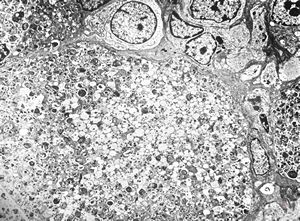

normal seromucinous salivary gland